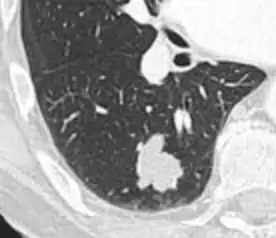

Calcifications and popcorn-like appearance, conferring a diagnosis of hamartoma.[9]

• In case of calcifications, a popcorn-like appearance indicates a hamartoma, which is benign.[3]